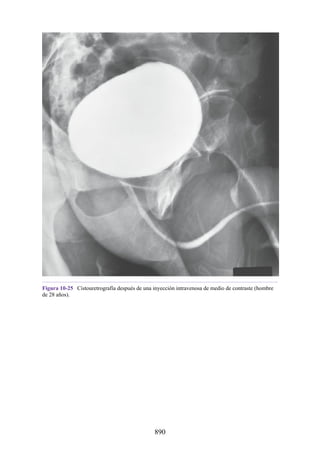

DISVISIÓN

PARASIMPÁTICA